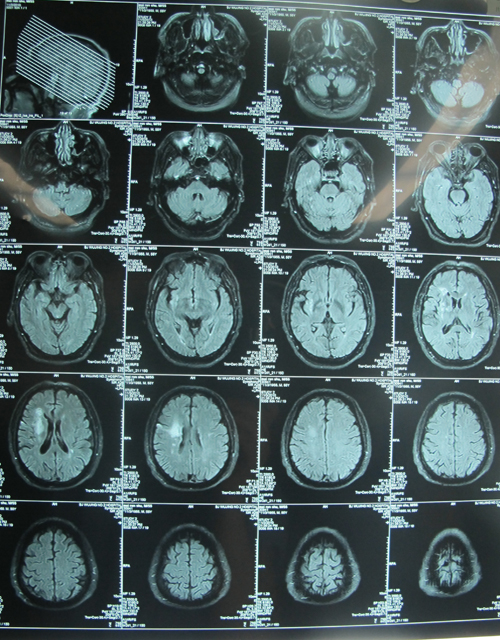

现病史:患者10余年前无明显诱因出现头晕,无耳鸣、恶心、呕吐,无视物模糊、视物旋转,无胸闷、胸痛,无心悸、气短,无意识障碍,无肢体、言语不利,休息后约10分钟上述症状可完全消失,此后头晕症状间断出现,性质同前,每次持续十余分钟至数小时不等,与头颈部活动无明显相关性,偶伴头痛,呈双太阳穴处波动性痛,于当地医院就诊,测血压为160/90mmHg,后多次测血压均高于140/90mmHg,最高位200/110mmHg,明确诊为高血压病,但患者未予重视,未规律用药,2年前开始规律服用络活喜5mg qd降压治疗,血压可控制在130-140/80mmHg左右。3个月患者无明显诱因出现头晕加重伴言语不利,右下肢力弱,无恶心、呕吐,无视物模糊、视物旋转,无胸闷、胸痛,无心悸、气短,无意识障碍,于当地医院就诊行头颅CT、MRI检查明确诊断为脑梗塞(右侧半卵圆中心、基底节区脑梗塞),经治疗后症状改善出院(具体不详),2周前于北京宣武医院、武警总队第二医院完善头颈部血管超声、MRA及血管造影检查提示右侧颅内血管多发狭窄,双侧颈动脉、椎动脉狭窄,以右侧颈动脉球部为著,狭窄约90%,建议行颈内动脉剥脱术,今日为进一步诊治收入院。患者自病情加重以来神清,饮食、睡眠及二便情况基本正常,近期体重无明显减轻。

该患者为老年患者,间断头晕10余年,加重伴言语不利、右下肢力弱3个月,右侧颈动脉球部狭窄约90%,且有高血压、糖尿病等危险因素,手术指征明确。2010年11月3日,由协作组张勤奕教授、王冬青教授及安贞医院欧阳川主任共同为其实施了右侧颈内动脉内膜剥脱术。术后患者恢复良好。